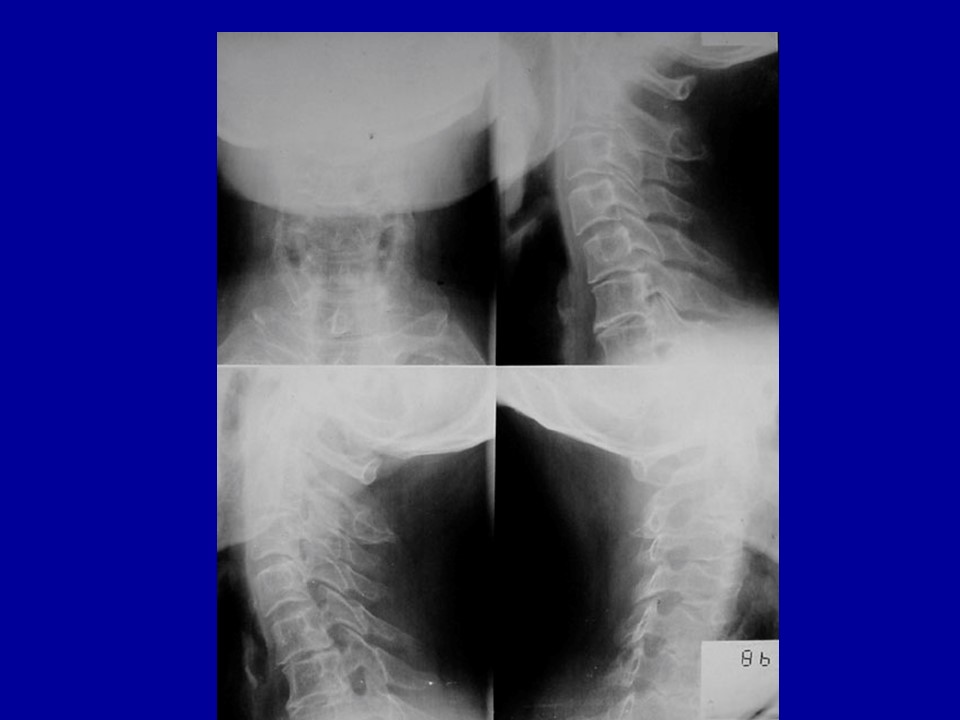

颈椎病的解剖及分型治疗PPT